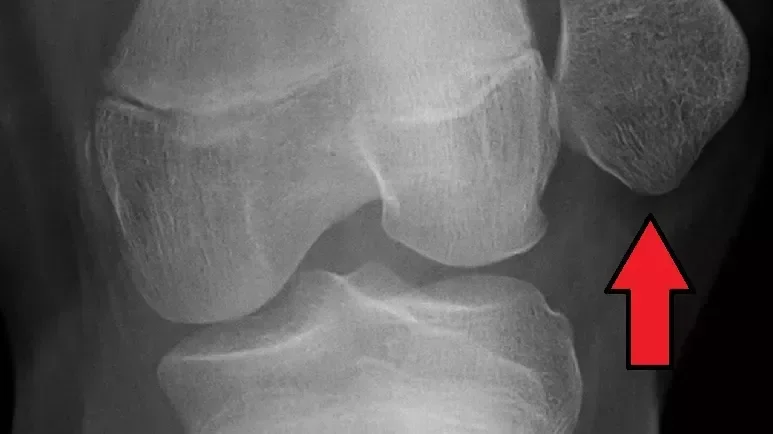

Poskodbe meniskusa

Poskodbe meniskusa - vzroki, simptomi, diagnostika in moznosti zdravljenja raztrganin meniskusa.